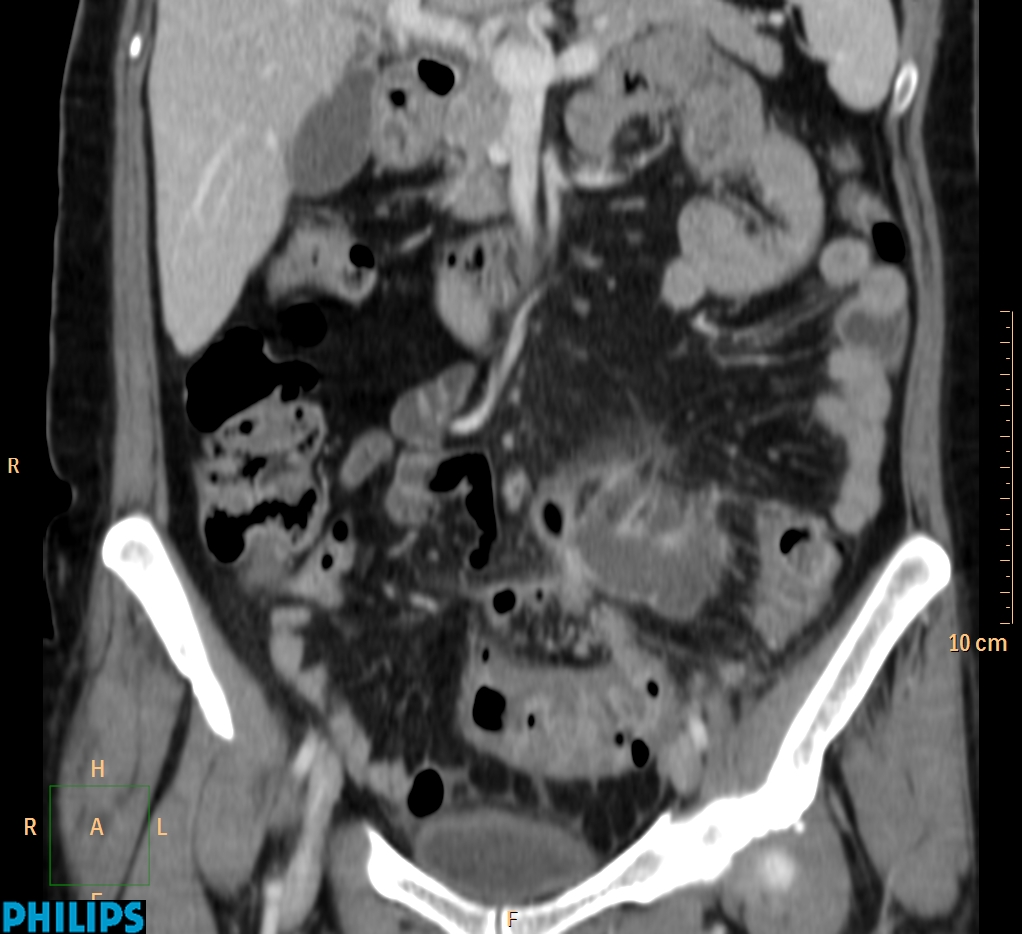

ΕΚΚΟΛΠΩΜΑΤΑ ΠΑΧΕΟΣ ΕΝΤΕΡΟΥ Posted by ΙΠΠΟΚΡΑΤΕΙΟ ΙΩΑΝΝΙΝΩΝ | Dec 16, 2020 | ΠΕΠΤΙΚΟ | 0 ΚΛΙΝΙΚΑ ΣΤΟΙΧΕΙΑ – ΙΣΤΟΡΙΚΟ υποτροπιάζοντες επαναλαμβανόμενοι πυρετοί κυρίως απογευματινές ώρες ΕΡΓΑΣΤΗΡΙΑΚΟΣ ΕΛΕΓΧΟΣ ΑΠΕΙΚΟΝΙΣΤΙΚΟΣ ΕΛΕΓΧΟΣ διακρίνονται τα αποστήματα στην ελάσσονα πύελο, καθώς και εκκολπώματα με εικόνα πάχυνσης του τοιχώματος του σιγμοειδούς ΣΥΖΗΤΗΣΗ